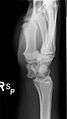

The lunate bone (semilunar bone) is a carpal bone in the human hand. It is distinguished by its deep concavity and crescentic outline. It is situated in the center of the proximal row carpal bones, which lie between the ulna and radius and the hand. The lunate carpal bone is situated between the lateral scaphoid bone and medial triquetral bone.

The lunate is a crescent-shaped carpal bone found within the hand. The lunate is found within the proximal row of carpal bones. Proximally, it abuts the radius. Laterally, it articulates with the scaphoid, medially with the triquetral, and distally with the capitate. The lunate also articulates on its distal and medial surface with the hamate bone.[1]:708[2]

The proximal surface of the lunate bone is smooth and convex, articulating with the radius. The lateral surface is flat and narrow, with a crescentic facet for articulation with the scaphoid. The medial surface possesses a smooth and quadrilateral facet for articulation with the triquetral. The palmar surface is rough, as is the dorsal surface. The dorsal surface is broad and rounded. The distal surface of the bone is deep and concave.[3]

The lunate bone is the most frequently dislocated carpal bone.